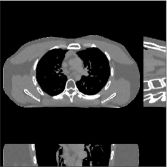

This section compares the reconstruction quality and runtime among the proposed MBIR method, PWLS-ST-, and other three MBIR methods, PWLS-EP, PWLS-DL, and PWLS-ST-. Table I shows that, for both 2D and 3D sparse-view CT reconstructions of the XCAT phantom, the proposed PWLS-ST- model outperforms PWLS-EP and PWLS-ST- in terms of RMSE. In addition, PWLS-ST- using a square transform (of size ) achieves lower RMSE than PWLS-DL using an overcomplete dictionary (of size ) for 2D sparse-view reconstructions. Fig. 3(a) and Fig. 4 show the reconstructed images for 2D and 3D phantom experiments, with different reconstruction models and different number of views. (See the corresponding error maps in the supplement.) The proposed PWLS-ST- consistently gives more accurate image reconstructions compared to other MBIR methods. Specifically, PWLS-ST- has smaller errors in the heart region (see zoom-ins in Fig. 3(a)) of 2D reconstructions than PWLS-DL and PWLS-ST-. In addition, compared to PWLS-ST-, PWLS-DL and PWLS-ST- have some ringing artifacts around the edges with high transition, e.g., edges between air and soft tissues. (See a comparison of profiles of PWLS-ST- and PWLS-ST- in the supplement.) In particular, PWLS-ST- and PWLS-DL give more visible ringing artifacts for 2D reconstruction from fewer views, and PWLS-ST- has these ringing artifacts for 3D reconstructions regardless of the number of views (see zoom-ins in Fig. 4). Table II reports runtimes of different MBIR methods in reconstructing the -views XCAT phantom scan. (FBPConvNet is a non-MBIR method and its runtime for processing a image is approximately one second with a TITAN Xp GPU.) While providing better reconstruction quality, the proposed Algorithm 1 of PWLS-ST- has shorter runtime compared to the algorithms of PWLS-DL and PWLS-ST- in Section III-A. Similar to the PWLS-EP algorithm, the reconstruction time of the PWLS-DL, PWLS-ST-, and PWLS-ST- algorithms can be further reduced by using ordered subsets [51].

Fig. 3(b) shows that when tested on the clinical scan data, the proposed PWLS-ST- method improves reconstruction quality in terms of noise and artifacts removal (e.g., see zoom-ins for soft-issue regions), and edge preservation (e.g., see zoom-ins for bone regions), compared to PWLS-EP and PWLS-ST-. Compared to PWLS-DL, PWLS-ST- achieves comparable image quality, but requires less computational complexity.

The benefit of the proposed PWLS-ST- over PWLS-ST- can be explained when there exist some outliers for some : in (12) gives equal emphasis to all sparse codes – from small to large coefficients that generally correspond to edges in low- and high-contrast regions, respectively – in estimating ; however, PWLS-ST- adjusts to mainly minimize the outliers, i.e., it may not pay enough attention to reconstruct regions with small coefficients. The histogram results in Fig. 1 reveal model mismatch of PWLS-ST- over the iterations. Fig. 3, Fig. 4, and Table I show that PWLS-ST- can moderate model mismatch, and provides more accurate reconstruction than PWLS-ST-.

![]() |

| (a) 2D fan-beam CT experiments |